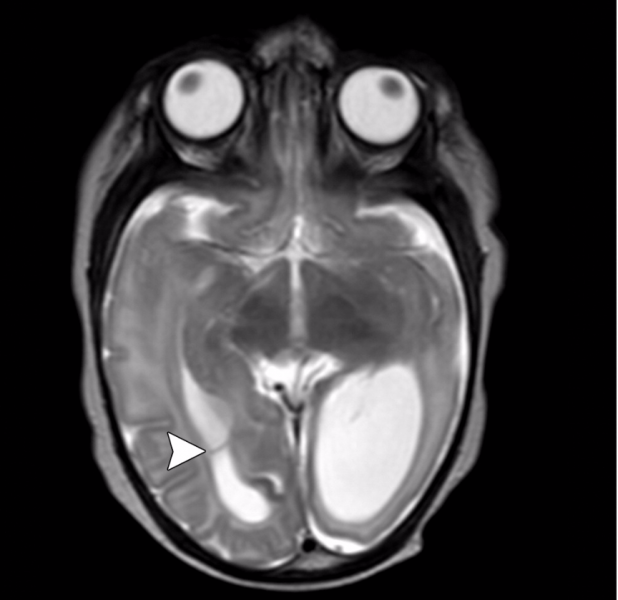

Though much of the concern in the media regarding the toxic effects of Zika virus has focused on brain findings of microcephaly, the researchers noted that there are a variety of brain abnormalities that can be found in fetuses exposed to the virus, including gray and white matter volume loss, brainstem abnormalities, calcifications and a condition called ventriculomegaly, where the ventricles, or fluid filled spaces in the brain, are enlarged. Some babies infected by Zika may not have a small head size if the ventricles remain excessively enlarged.

The brain abnormalities seen in confirmed and presumed Zika groups were very similar. Nearly all of the babies in each group had ventriculomegaly. Although most fetuses had at least one exam showing abnormally small head circumference, the researchers discovered that head circumference was normal in three fetuses with severe ventriculomegaly.

Ninety-four percent of the confirmed Zika group and 79 percent of the presumed Zika group had abnormalities of the corpus callosum, which is a large nerve fiber bundle that allows communication between the left and right hemispheres of the brain. All but one had cortical migrational abnormalities, meaning the neurons did not travel to their proper destination in the brain.

Intracranial calcifications were present in almost all of the neonates, most commonly found at the gray-white junction of the brain. All of the babies exhibited reduced tissue volume in their brains. All patients showed varying abnormalities in cortical development.

“The severity of the cortical malformation and associated tissue changes, and the localization of the calcifications at the grey-white matter junction were the most surprising findings in our research,” Tovar-Moll said.